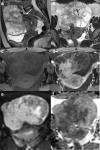

Although rare, uterine sarcoma is a diagnosis that no one wants to miss. Often benign leiomyomas (fibroids) and uterine sarcomas can be differentiated due to the typical low T2 signal intensity contents and well-defined appearances of benign leiomyomas compared to the suspicious appearances of sarcomas presenting as large uterine masses with irregular outlines and intermediate T2 signal intensity together with possible features of secondary spread. The problem is when these benign lesions are atypical causing suspicious imaging features. This article provides a review of the current literature on imaging features of atypical fibroids and uterine sarcomas with an aide-memoire BET1T2ER Check! to help identify key features more suggestive of a uterine sarcoma.